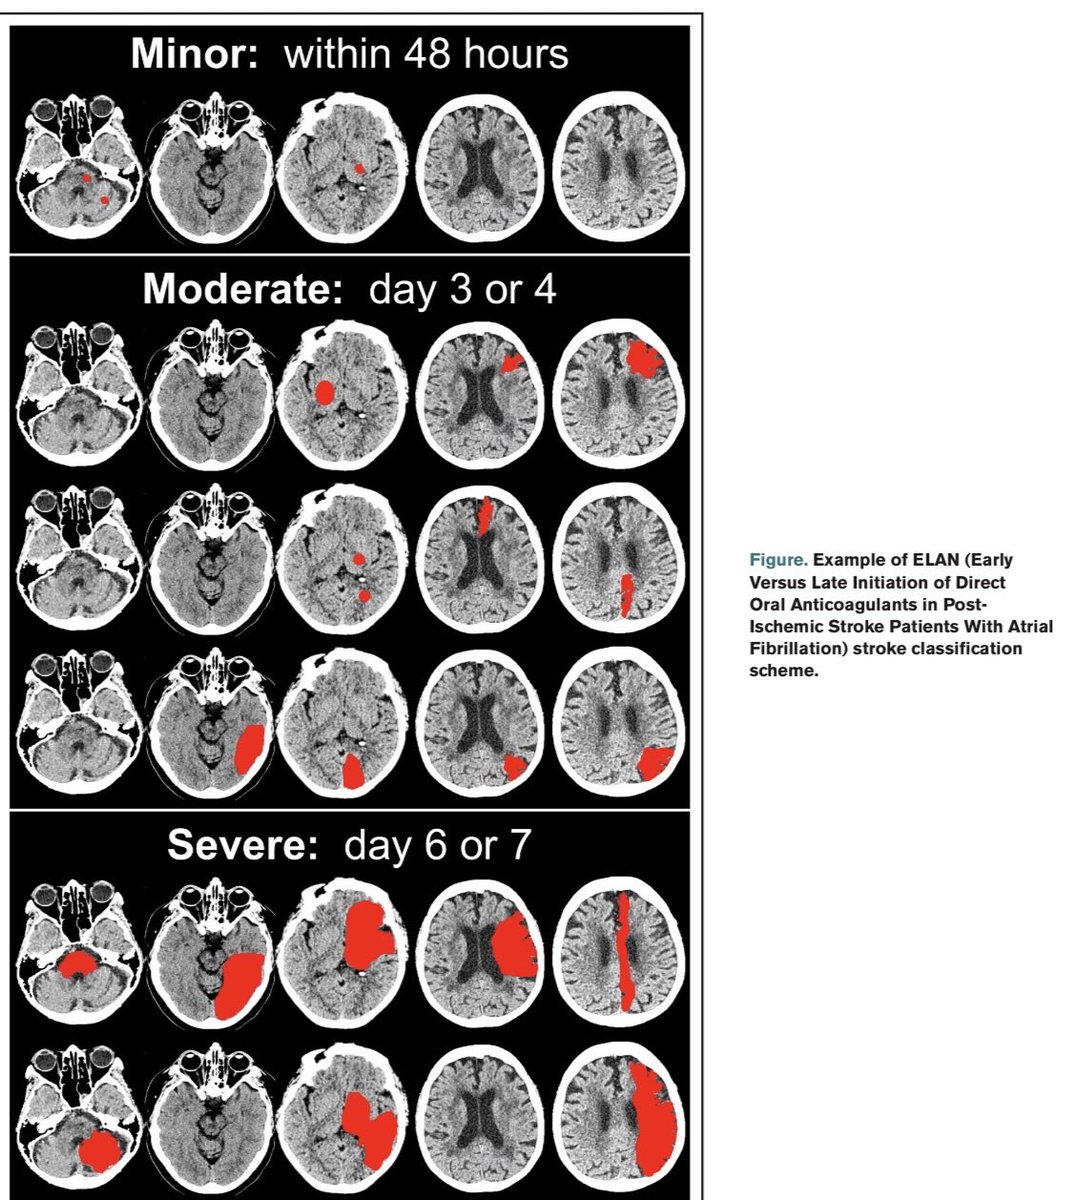

‼️ Momento de iniciar la anticoagulación en pacientes con EVC isquemico y FA 📚 Artículos a leer: ELAN,ÓPTIMAS,CATALYST,TIMING,START ✅ Inicio de anticoagulacion: Menor 48 hrs Moderado 3 o 4 días Severo 6 a 7 días